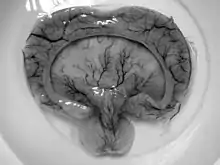

Gross pathology specimen from a case of alobar holoprosencephaly, a clinical manifestation of Young–Madders syndrome first described as a new condition by doctors Young and Madders in 1987. |

Young–Madders syndrome is detectable from the fetal stage of development largely due to the distinctive consequences of holoprosencephaly, a spectrum of defects or malformations of the brain and face. Facial defects which may manifest in the eyes, nose, and upper lip, featuring cyclopia, anosmia, or in the growth of only a single central incisor, and severe overlapping of the bones of the skull.[2][3] Cardiac and in some cases pulmonary deformities are present.[2] Another signature deformity is bilateral polydactyly, and many patients also suffer from hypoplasia and genital deformities.[1]